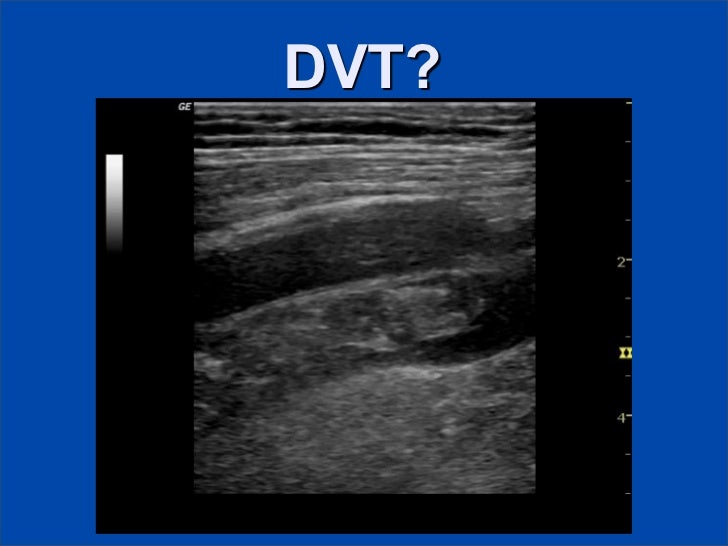

Nonocclusive thrombus means there is a clot that is not totally obstructing the vein.

Dvt on its own can be occlusive if the whole circumference of the blood vessel is involved or if there is passage of blood through it is non occlusive. DVT can be classified as occlusive or nonocclusive thrombus. However thrombolysis does not always lead to rapid resolution of clot and carries an increased risk of haemorrhage.

Evidence-based information on non occlusive dvt from hundreds of trustworthy sources for health and social care. Deep vein thrombosis DVT is a condition of having a stationary blood clot known as a thrombus in the deep veins of the arms or legs. Nonocclusive thrombus 4 mm thickness.